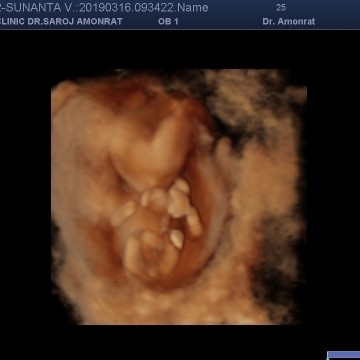

คุณแม่ช่วยดูหน่อยค่ะ ว่าเพศอะไรค่ะ

คุณแม่ช่วยดูหน่อยค่ะ ว่าเพศอะไรค่